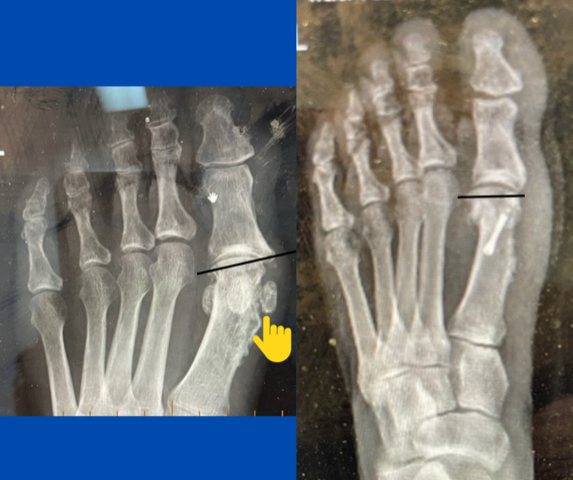

Severed tendon

By |June 26th, 2023|

Blog's main page This patient presented with a painful enlarged 2nd MTPJ, but her main concern was the fact that the associated 2nd toe is "floppy" and catches on the [...]